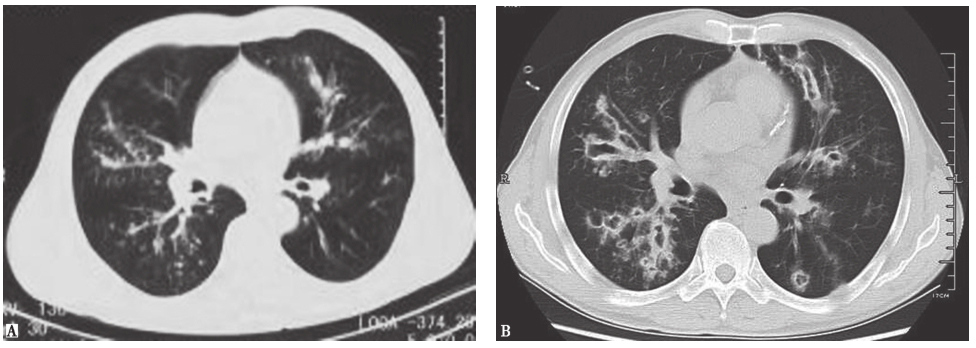

图2侵袭性肺曲霉菌病胸部CT表现

男性患者,53岁,发热、咯血1周,伴呼吸困难,诊断为侵袭性肺曲霉菌病。胸部CT初期表现为沿支气管分布的粟粒样结节(A);1周后表现为多发沿支气管分布的空洞,有中心性支气管扩张(B)

图3血源性金黄色葡萄球菌肺炎胸部CT表现

胸部CT可见双肺多发结节空洞性改变,部分空洞伴液平,病灶周围可见渗出表现